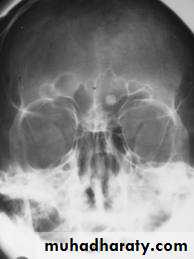

General blood investigations (CBP, ESR, Renal function test...etc) (as a preoperative measure and to detect distant metastasis)Plain X-ray of nose & Paranasal sinuses (occipto-mental view). Shows opacification of the sinus and bone erosion.

CT scan & MRI: show the tumor, bone erosion& extension of the tumor.